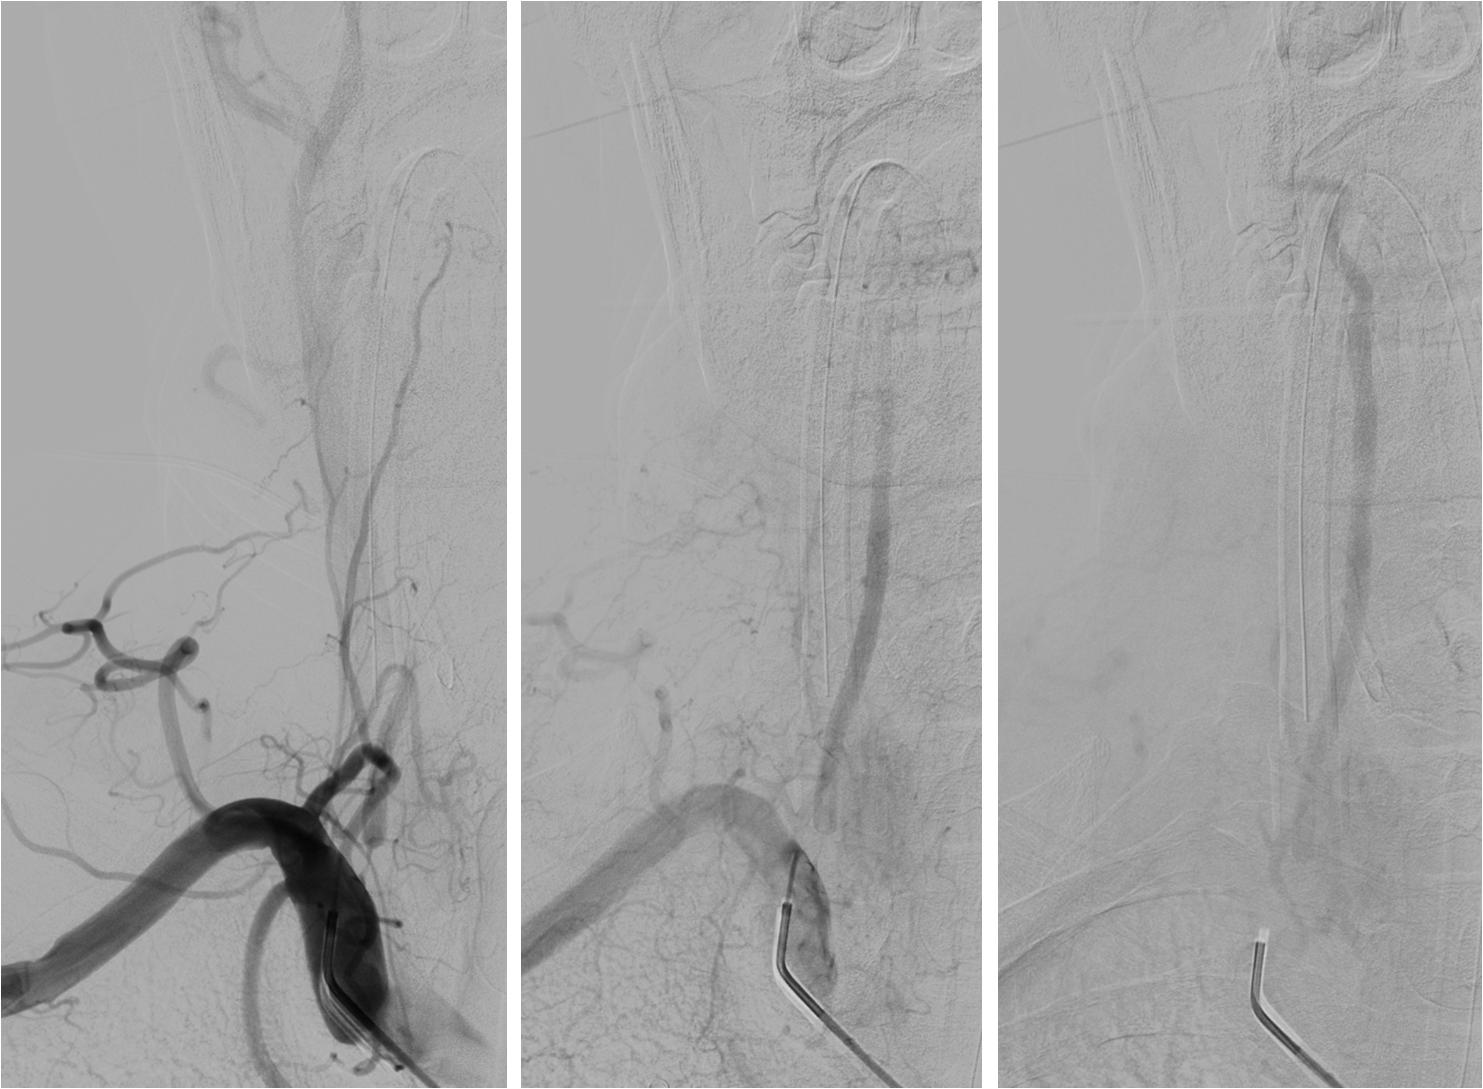

》13:22进入导管室行血管内治疗。行气管插管全身麻醉。

》DSA见基底动脉闭塞,Solitaire支架取栓后见基底动脉重度狭窄,Gateway球囊扩张,置入Wingspan支架。

》术后24h完全恢复,NIHSS评分0分。

▼13:49DSA

▼支架取栓后基底动脉残余重度狭窄

▼基底动脉支架置入术